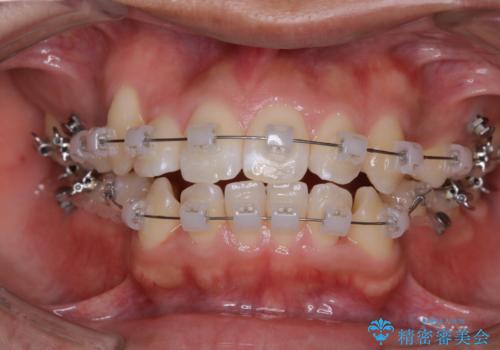

- 矯正装置

- クリア装置

親知らずと、前から4番目の歯を抜歯してワイヤー装置による矯正治療を行いました。

人前に出ることが多いため、当初は目立たない装置をご希望されていましたが、歯の移動距離が大きいため効率よく歯を動かせる表側の装置での治療をお勧めしました。すれ違ってしまっていた奥歯もしっかり治すことができました。